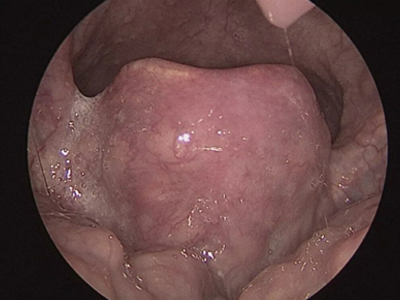

急性会厌炎是会厌及周围软组织的迅速肿胀,并可引起致命的呼吸道突然阻塞。又称为急性声门上喉炎,是会厌的急性感染,炎症发生部位以会厌为主,可向杓会厌襞以及声门上区蔓延。成人及儿童均可发病,但以成人较多见,男性多于女性,常发生于早春与秋末。

急性会厌炎起病急骤,有畏寒、发热、头痛等全身不适,多数患者体温在38-39℃。以剧烈的咽喉疼痛为主要症状,吞咽时加剧,重者饮水呛咳、流涎。喉镜下可见会厌舌面黏膜充血,高度肿胀水肿呈圆球状如卷曲香肠,肿胀可偏于一侧,偶见有黏膜溃疡。